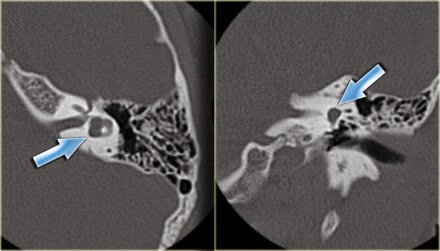

Colesteatoma: Acumulo

anormal de epitelio escamoso queratinizado, el cual reemplaza a la mucosa

normal. La mayoría se considera como adquirido, aunque en ocasiones se presenta

como una anomalía congénita.

Se ubicada en el espacio de Prusak y produce erosión ósea en el scutum y de la pared del canal semicircular lateral.